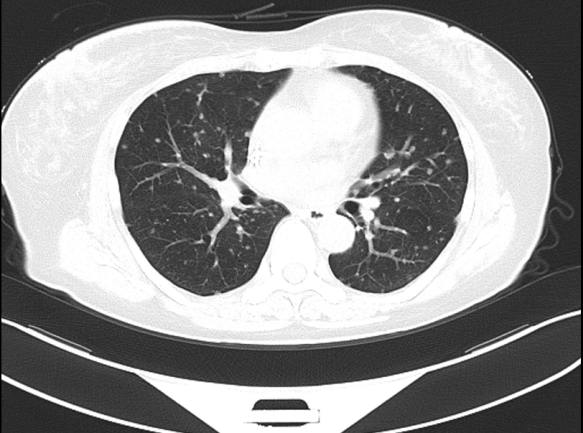

④三线治疗:曲妥珠单抗(汉曲优) 300mg Q3W+吡咯替尼 320mg QD+唑来膦酸4mg Q3M,并予以局部区域放疗。维持治疗至2022.03.31出现新发左肺转移灶及右侧小脑转移灶。行支气管镜检查,并取左肺下叶背段支气管开口见新生物活检,病理提示:(左肺结节)乳腺癌转移,Ki-67(20%,+),ER(-),PR(-),HER2(3+)。右侧小脑异常信号,1.2cm(图5),考虑转移。疗效评价PD,PFS 16个月。

图5. 2022.03左肺及右侧小脑影像图

两个疗程后评估:左肺下叶转移灶较前缩小,1.1cm;右侧小脑转移灶较前缩小,0.8cm(图6)。疗效评价 PR,继续维持该方案。

图6. 2022.05左肺及右侧小脑影像图